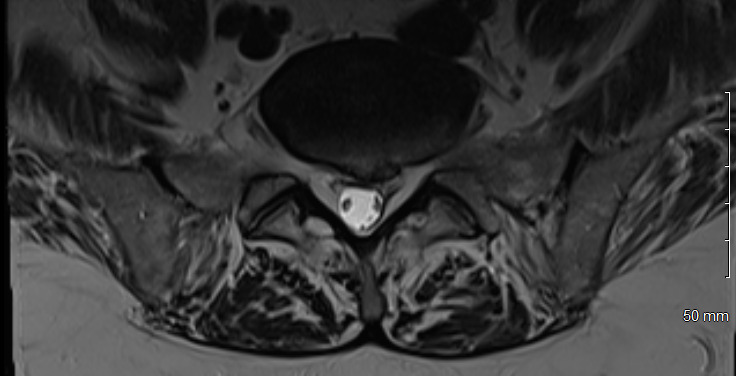

Physical examination revealed hypertonicity and tenderness in the lumbar paraspinal muscles and the left posterior hip region. He reported a pain level of 8/10 on the NPRS, reflecting both LBP and radicular symptoms. Additionally, a score of 32 out of 40 on the DVPRS indicated substantial pain-related functional impairment. A 2024 lumbar spine MRI demonstrated degenerative disc disease, arthropathy, severe left subarticular recess stenosis at L4-L5 with L5 nerve impingement, and a small left central disc extrusion at L5-S1 abutting the S1 nerve root (Figs. 1–4).

This case report documents an unexpected improvement in PLP during chiropractic treatment for LBP and radicular symptoms in a patient with a below-knee amputation. The temporary abolition of PLP reported at Visit 5, which was sustained for 2 weeks, suggests that automated lumbar long-axis distraction and myofascial release may influence the neuropathic pain pathways in amputee patients. Furthermore, lumbar distraction may reduce mechanical compression on the L5 nerve root, as seen on MRI (Figs. 1-4), potentially decreasing spinal cord hyperexcitability associated with PLP.15 Myofascial release, by addressing trigger points and muscle tension, may alter afferent input to the spinal cord, influencing pain processing.16 Chiropractic manipulation has been shown to modulate pain perception and widespread pressure sensitivity, likely through activation of descending inhibitory pathways. While these mechanisms may play a role in conditions involving central sensitization, their relevance to neuropathic pain such as PLP needs further investigation.17